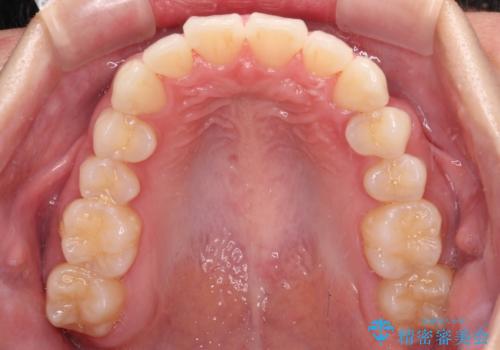

思っていたよりも早くクロスバイトは改善され、歯髄壊死に至ることなく、無事に治療を終えることができました。

- 1年6ヶ月